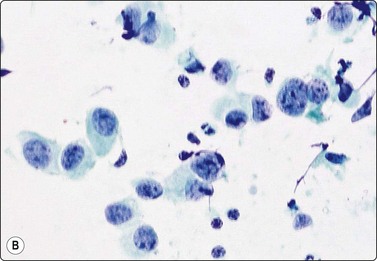

Breast tissue in pregnancy and lactation (Fig. 7.8)

image image image

Fig. 7.8 Lactating breast

Dispersed acinar cells with abundant pale and fragile cytoplasm, rounded nuclei and prominent central nucleoli; background of lipid secretions (A, MGG, HP; B, H & E, HP oil); (C) Corresponding tissue section (H&E, IP).

Criteria for diagnosis

Cellular smears,

Poorly cohesive, mainly dispersed epithelial cells of acinar type,

Cells have abundant fragile cytoplasm with secretory vacuoles and frayed borders,

Rounded vesicular nuclei and central nucleoli,

Dirty background due to lipid secretion and stripped nuclei with prominent nucleoli,

Single bipolar nuclei difficult to find.

FNB is very useful in reducing surgical intervention to a minimum during pregnancy and lactation. The pattern seen in FNB smears of ‘lumps’ in a pregnant or lactating breast can be problematic to inexperienced eyes and cause concern for malignancy.93,94 Smears are usually cellular. The cells are enlarged and arranged in loose groups or singly. The cells have an abundant fragile cytoplasm, vacuolated and finely granular. Nuclei are round, central, larger than the usual ductular cells, and have distinct small nucleoli (Fig. 7.8B). Some epithelial nuclei are stripped of cytoplasm. Single naked bipolar/oval nuclei are difficult to find. The background of abundant milky secretion with numerous lipid droplets seen as vacuoles is characteristic of actively secreting breast tissue and is the main clue to the diagnosis (Fig. 7.8A).